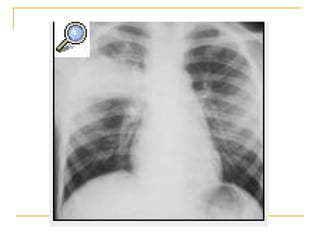

Radiografía de tórax obtenida al ingreso (compromiso intersticial   )

Radiografía de tóraxobtenida al ingreso (compromiso intersticial )